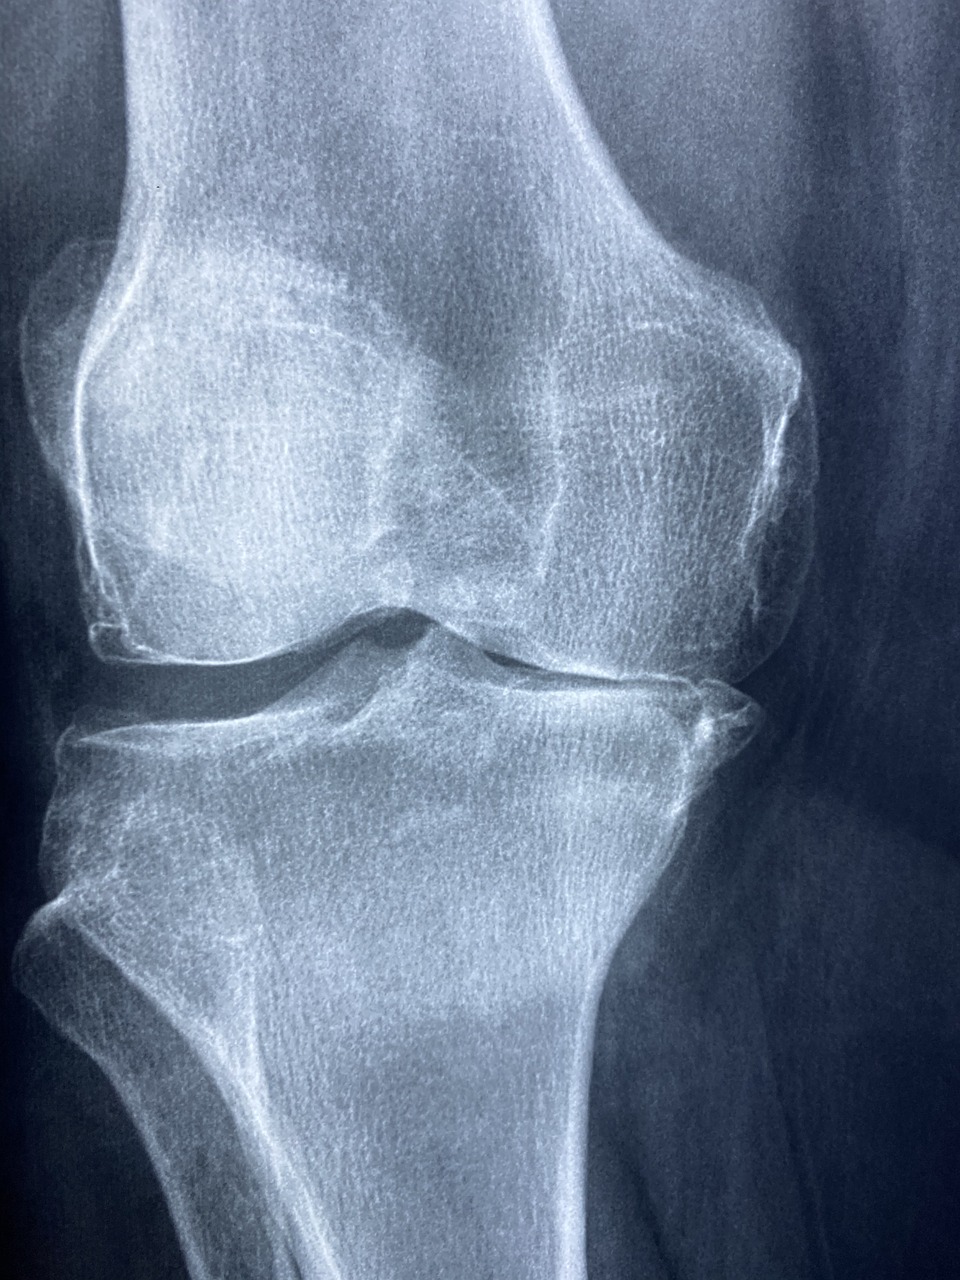

📌 무릎 인공관절 수술비 지원

- ✔ 한쪽 무릎: 최대 120만 원 지원

- ✔ 양쪽 무릎: 최대 240만 원 지원

무릎 인공관절 수술 후 초기 회복, 중기, 장기 관리

무릎 인공관절 수술은 심한 무릎 관절염이나 관절 손상으로 인해 일상생활이 어려운 환자들에게 시행되는 치료법입니다. 손상된 관절을 제거하고 인공 관절을 삽입함으로써 통증을 줄이고 관